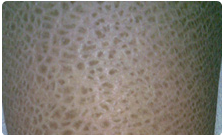

鱼鳞病是一种常见的遗传性皮肤角化障碍性疾病,旧称鱼鳞癣,中医称蛇皮癣。多于儿童时发病,是一种遗传性角化障碍性皮肤病,其特点为四肢伸侧或躯干部发生很多干燥、粗糙状如鱼鳞的、角化性鳞屑、有深重斑纹、好起白皮。寒冷干燥季节加重。好治而容易复发。

1、寻常性鱼鳞病:轻者皮肤干燥、粗糙、少量鳞屑,重者皮肤伴有糠秕状鳞屑,呈菱形或多角形,淡褐色或深褐色,状如鱼鳞,四肢伸侧。